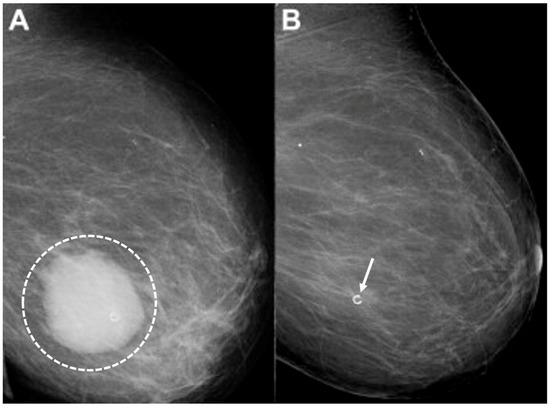

Ultrasound of the breast. Office-based cryoablation is optimized for treatment of ultrasound-visible breast cancers. Consequently, breast ultrasound should be performed of all suspicious imaging abnormalities to assess eligibility for ultrasound-guided cryoablation. Ultrasound permits assessment of the cancer’s proximity to the overlying skin and underlying chest wall and also enables detection of changes in adjacent tissue architecture (e.g., edema, tissue distortion, extension of tumor into adjacent ducts) and could indicate the presence of more extensive disease that would need to be incorporated into the treatment plan (Figure 2). Proximity (<5 mm) of a cancer to the skin is generally regarded as a contraindication to cryoablation, but a safe skin distance can sometimes be created using hydrodissection or injection of saline between the tumor and overlying dermis.

Figure 2.

(A) shows dark, dominant, irregular mass encircled by hash marks with intraductal tumor extensions (dark bands bracketed by paired arrows) extending from left and right sides of dominant mass. (B) shows dark, irregular dominant mass (arrow) surrounded by peri-tumoral edema outlined by hash marks.